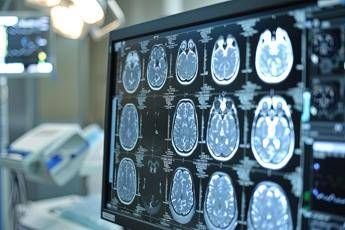

Neoplasie cerebrali, in Italia ogni anno 3mila casi di glioma

(Adnkronos) – Una volta erano considerate delle neoplasie rare, ma oggi i gliomi sono sempre più diffusi. In Italia i casi annui ammontano a oltre 3mila e corrispondono al 40% di tutti i tumori cerebrali primitivi. Tra i gliomi, quelli di basso grado di frequenza più rara rappresentano una sfida clinica rilevante anche per la loro evoluzione e l'assenza di trattamenti mirati, oltre alla resistenza che dimostrano ai trattamenti convenzionali. Sono malattie orfane di cui si parla poco anche fra i clinici, tra le istituzioni e sui media. Perciò la Fondazione Aiom (Associazione italiana di oncologia medica) ha lanciato nei mesi scorsi 'I gliomi', una campagna nazionale online di formazione e informazione. Sono stati organizzati webinar rivolti agli oncologi medici e alle altre figure sanitarie coinvolte nel team multidisciplinare. Sono stati indirizzati a pazienti e caregiver ulteriori eventi online insieme a un'attività di sensibilizzazione sui principali social media. I risultati dell'iniziativa sono presentati oggi in una conferenza stampa virtuale promossa da Fondazione Aiom. Il progetto è stato realizzato con il contributo non condizionante del Gruppo Servier in Italia.  "Sono tumori cerebrali molto complessi e che spesso vengono diagnosticati in età giovanile – afferma Saverio Cinieri, presidente di Fondazione Aiom – Si sviluppano da cellule del cervello chiamate gliali e possono avere una prognosi variabile, ma potenzialmente a lungo termine. La gestione della patologia richiede una stretta collaborazione fra neurochirurgo, radioterapista e oncologo medico. Attraverso il bisturi è possibile rescindere la massa tumorale oppure eseguire una biopsia grazie a nuove e sofisticate tecnologie. La radioterapia permette di ridurre il rischio di recidiva o eliminare quella parte di cancro che non è stato possibile rimuovere chirurgicamente. Viene somministrata insieme alla chemioterapia e le sedute sono di solito diluite nel corso del tempo, per limitare l'impatto degli effetti collaterali. Infine, l'oncologo medico deve scegliere i farmaci da somministrare e deve selezionarli valutando le condizioni cliniche del singolo paziente".  "Anche per il trattamento dei gliomi, in particolare quelli di basso grado, si può ricorrere all'oncologia di precisione che potrà ridisegnare la pratica clinica nel prossimo futuro – illustra Enrico Franceschi, direttore dell'Oncologia del sistema nervoso all'Irccs Istituto delle scienze neurologiche di Bologna – E' molto importante verificare la presenza o meno delle mutazioni Idh1 e Idh2. Questi biomarcatori indicano specifiche patologie caratterizzate da una prognosi decisamente più favorevole e maggiore sensibilità dei gliomi alla radio e chemioterapia. Al momento della diagnosi è quindi essenziale l'esecuzione precoce di alcuni test molecolari per identificare al meglio i diversi sottotipi di gliomi. Tra le terapie di nuova generazione vi è anche vorasidenib, un farmaco orale inibitore Idh1 e Idh2 che ha dimostrato di essere un trattamento efficace nel posticipare la radio e chemioterapia nei gliomi di basso grado ed è una rilevante innovazione medico-scientifica".  "Come tutti i tumori cerebrali – prosegue Cinieri – anche i gliomi di basso grado hanno un forte impatto sulla vita del paziente. Sono tante le complicanze che possono verificarsi durante l'intero percorso di cura, perché intervenire sul cervello umano con radiazioni ionizzanti o con interventi chirurgici può comprometterne alcune funzioni basilari. Tra queste vi sono le capacità di parlare o di movimento. Si rendono a volte necessari interventi riabilitativi di logopedisti, fisioterapisti o altri professionisti come lo psiconcologo. Ricevere la notizia della presenza di un tumore in una zona così particolare e delicata porta quasi sempre a depressione e ansia, soprattutto quando il primo approccio è un periodo di osservazione privo di un trattamento attivo. Le terapie innovative sono in grado di prolungare in modo significativo la sopravvivenza libera da progressione e garantiscono un buon profilo di sicurezza e tollerabilità". "Ancora una volta l'oncologia medica è centrale nella gestione multidisciplinare di neoplasie estremamente complesse ed insidiose – sottolinea Franceschi – Il trattamento dei gliomi inizia nel momento della diagnosi che deve essere sia morfologica che molecolare. Esistono infatti 150 diversi sottotipi di neoplasia cerebrale ed è fondamentale riconoscere fin da subito le caratteristiche del singolo caso per poter così selezionare le terapie più appropriate. Fino a pochi anni fa avevamo a disposizione solo chirurgia, radioterapia e chemioterapia. Ora i farmaci ad azione mirata sono una realtà anche nella cura dei tumori cerebrali che esprimano specifiche alterazioni molecolari".  "Nasce da questo rapido progresso nei trattamenti la nostra campagna d'informazione rivolta principalmente a specialisti clinici e pazienti – conclude Cinieri – L'oncologia medica è in costante evoluzione ed è compito di associazioni e fondazioni garantire sempre un aggiornamento scientifico qualificato. L'oncologia di precisione è una realtà consolidata in molte forme di cancro ed è un approccio che indirizza sempre più le nostre scelte terapeutiche. Sta portando a risultati davvero interessanti ed inimmaginabili fino a pochi anni fa anche per neoplasie rare e difficili da trattare come i gliomi di basso grado Idh mutati".